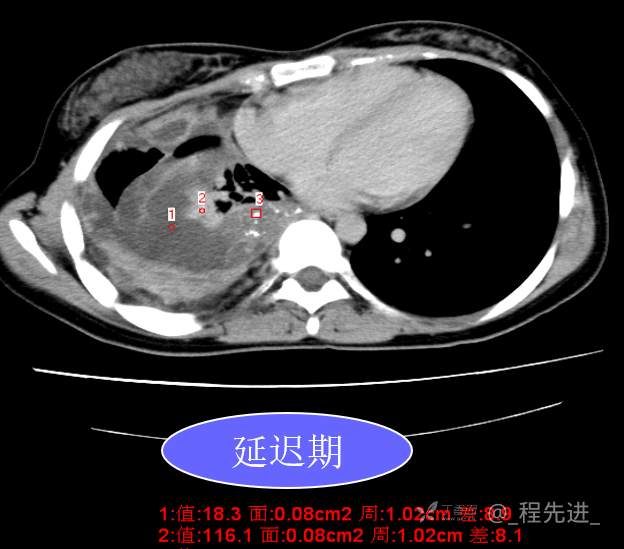

患者性别:女

患者年龄:26岁

简要病史:反复胸闷、气喘、咳嗽半年